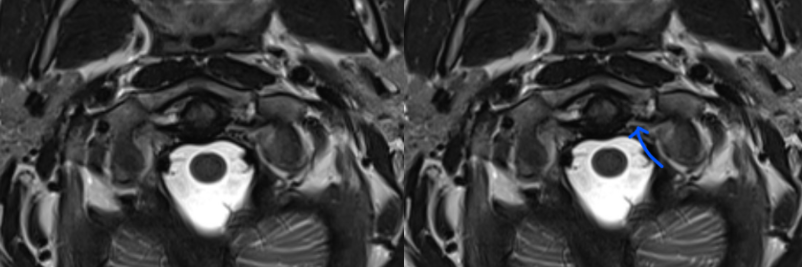

MRI

MRI demonstrating intra-ligamentous injury (blue arrow)

Jefferson MRI 1Jefferson MRI 2

MRI demonstrating avulsion of the TAL on the left side